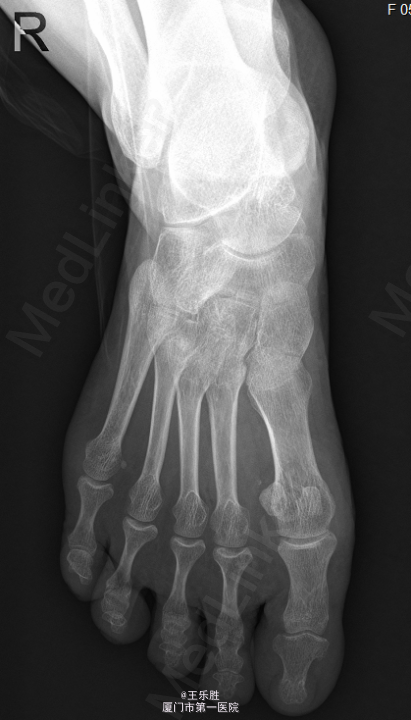

患者,女,58岁,因“右足跖趾关节酸痛半年”入院。

右足第一跖趾关节前侧可见红肿,关节处无明显压痛,关节活动尚可,足背动脉可及,足趾伸屈正常。远端血循良好,感觉正常。我院 MRI示右足第1跖趾关节积液,滑膜炎考虑。

初步诊断:右足第一跖趾关节滑膜炎.行“右第1跖趾关节滑膜切除+关节清理+骨赘切除术 ”.